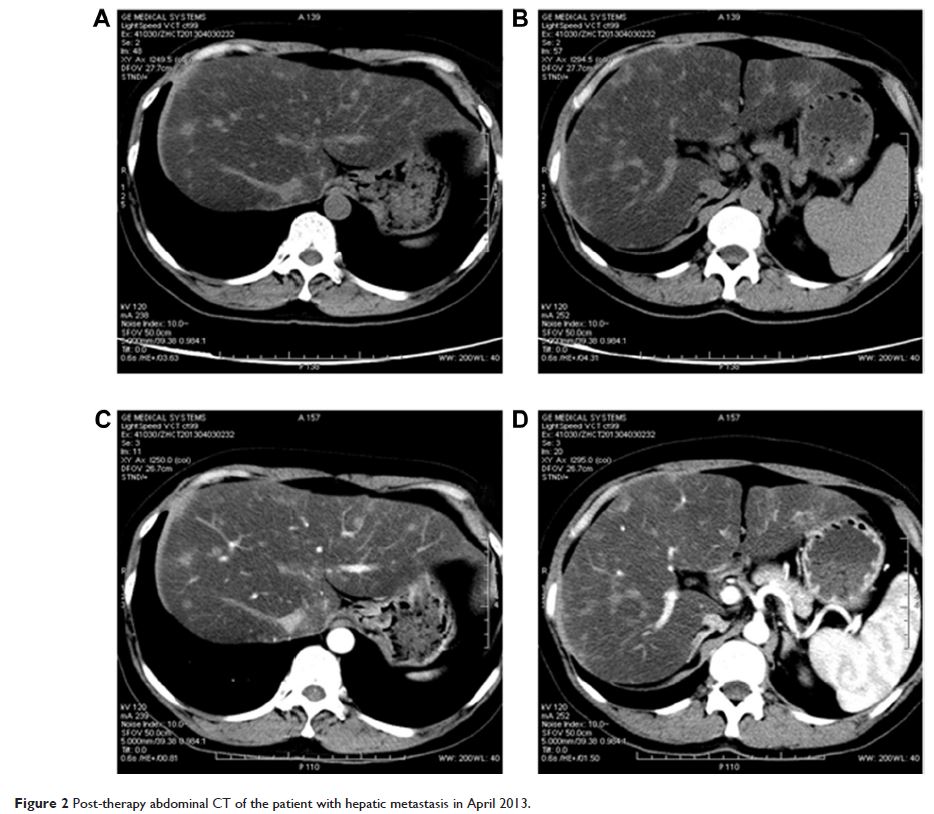

Case Series

- 作者:Shen-Cun Fang, Hai-Tao Zhang, Ying-Ming Zhang, Wei-Ping Xie

- 期刊:OncoTargets and Therapy